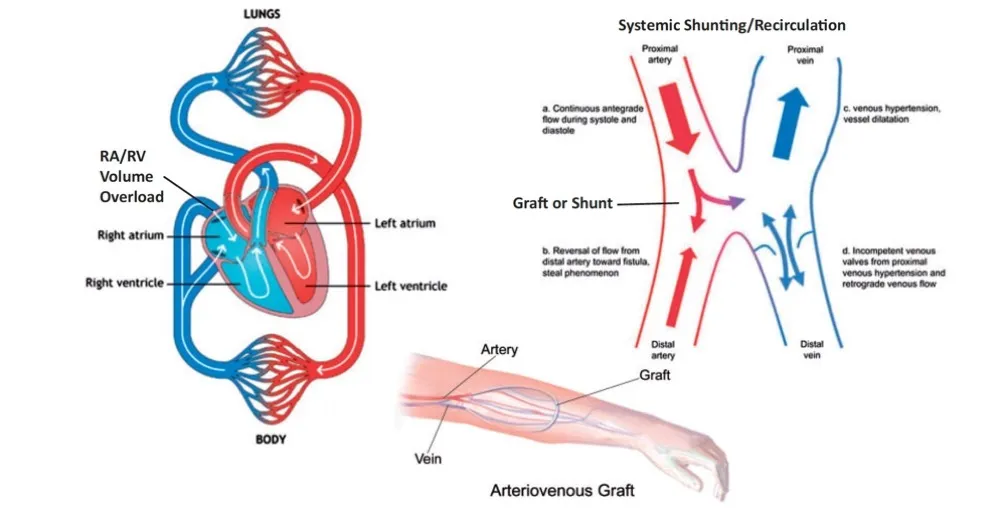

A criação de uma FAV desencadeia mudanças hemodinâmicas significativas, reduzindo a resistência vascular

sistêmica e aumentando o débito cardíaco. Essas alterações podem ser especialmente problemáticas em pacientes com doenças cardíacas preexistentes ou em casos em que o fluxo de acesso AV excede 2 L/min. É muito importante monitorar regularmente esses pacientes para identificar precocemente sinais e sintomas de insuficiência cardíaca (nem toda hipervolemia é transgressão de dieta!)

1. Aumento Imediato do Débito Cardíaco: Logo após a criação da FAV, há um aumento no débito cardíaco devido à baixa resistência vascular da fístula. Isso pode levar a alterações hemodinâmicas significativas, especialmente em pacientes com doença cardíaca preexistente (não foi o caso do nosso paciente)

3. Sobrecarga de Volume: Um aumento agudo no retorno venoso pode levar à sobrecarga de volume, especialmente se o paciente já tiver comprometimento da função cardíaca.

4. Alterações na Perfusão Distal do Membro: Pode ocorrer isquemia distal ou síndrome do roubo de fluxo, caracterizada por uma diminuição do fluxo sanguíneo para a mão e os dedos.

1. Remodelamento Cardiovascular: Com o tempo, o aumento crônico do débito cardíaco e do volume de retorno venoso pode levar ao remodelamento do coração, resultando em hipertrofia do ventrículo esquerdo e, eventualmente, insuficiência cardíaca.

Exame e oclusão transitória do acesso AV

A presença de uma FAV grande e distendida ou de um enxerto AV com aumento de pulso muito forte sugere fluxo sanguíneo elevado e deve levar a uma avaliação para determinar o efeito do acesso na hemodinâmica sistêmica. Quando a FAV é ocluída transitoriamente (30 segundos), o grau de aumento (aumento) do pulso

arterial distal à anastomose AV é proporcional ao fluxo arterial.